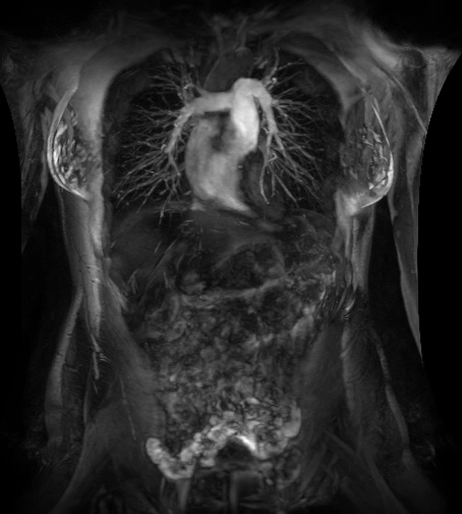

在乳腺M(fèi)R檢查中,SIGNAWorks?通過(guò)可調(diào)節(jié)線圈元件使得乳腺成像實(shí)現(xiàn)定量化和個(gè)性化,從而實(shí)現(xiàn)精準(zhǔn)醫(yī)療。創(chuàng)新型應(yīng)用——用于超快速動(dòng)態(tài)掃描的DISCO,用于高分辨率形態(tài)成像的Cube T2 with HyperSense和Cube T2 HyperCube,縮短了掃描時(shí)間并促進(jìn)了擴(kuò)散技術(shù)(Focus和MUSE)的發(fā)展,利用與BIRADs一致的CADStream來(lái)探測(cè)組織特征和分析。